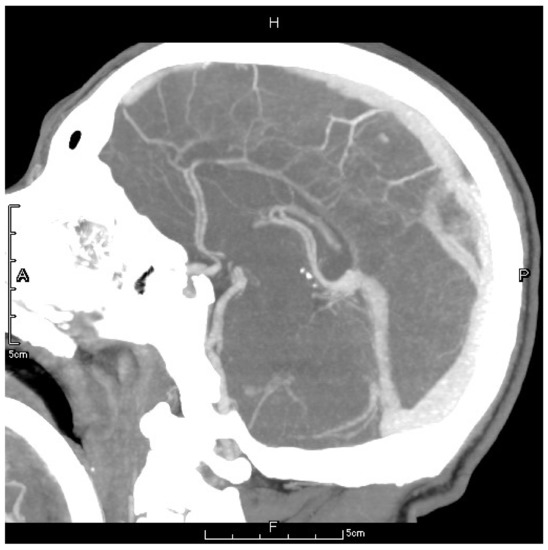

Figure 3.

The letter F, A, P, H in the figures refers to Foot, Anterior, Posterior and Head, respectively. Preoperative CTV showed a local patchy filling defect shadow behind the superior sagittal sinus which should be considered as thrombus formation.